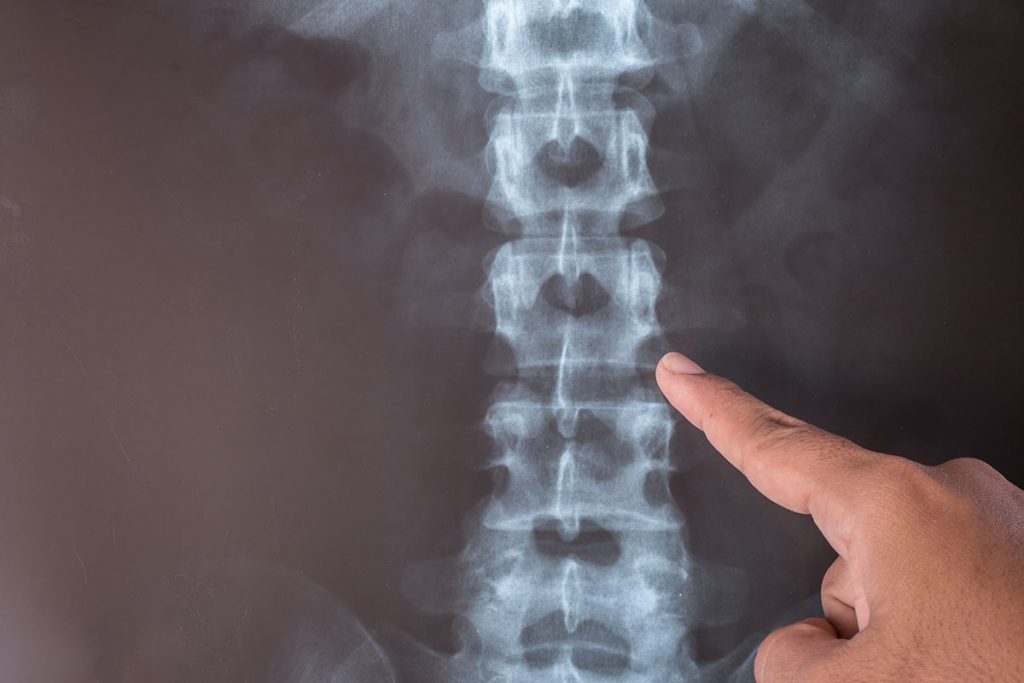

The spine has normal curves, but it appears straight when you look at someone’s back. However, some people, especially children and teens, develop an abnormal C-shaped or S-shaped curve in the spine. Most cases of scoliosis are idiopathic. This means there is no known cause. Is scoliosis preventable? Though it is not possible to prevent scoliosis, it is possible to prevent scoliosis from getting worse.

- X-ray images can confirm the presence of scoliosis and the degree of spinal curvature. A Cobb angle (curvature) greater than 10% indicates scoliosis is developing.

- The EOS scan, a 3-D imaging system, offers visualization of the spine’s curvature.